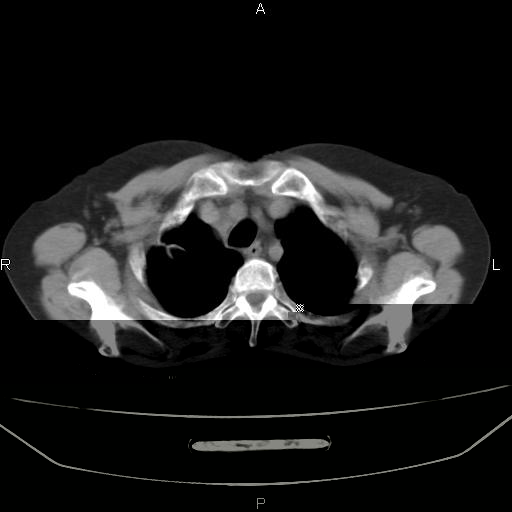

考虑:右肺上叶周围型肺癌(分叶状肿块+砂粒状钙化+胸膜尾征)。

病灶见明显分叶、大小较大(大于3cm?),老年人,多考虑:肺癌,建议穿刺活检。

右肺上叶周围型肺癌可能性大。

考虑:右肺上叶周围型肺癌